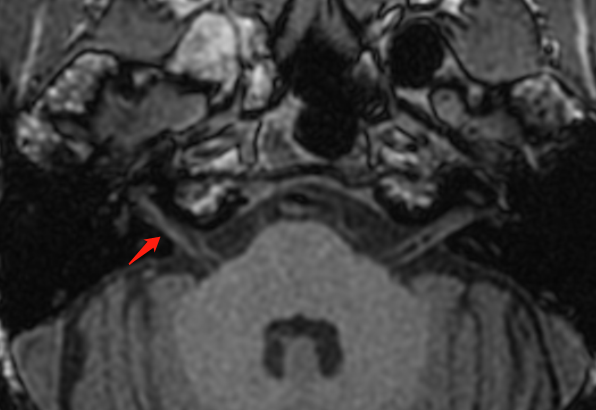

3DT1BRAVO 增强右侧前庭耳蜗神经轻度强化,延迟持续强化。

前庭耳蜗神经延迟强化,右小脑前下动脉迂曲进入内听道